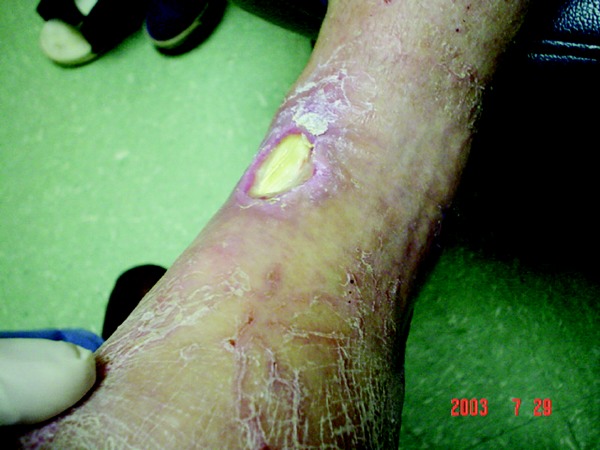

While there is quite an array of choices when it comes to choosing appropriate wound care modalities for lower-extremity wounds, there is not, as one panelist points out, a lot of published evidence for guidance. With this in mind, our expert panelists discuss a variety of wound care scenarios and how their clinical experience guides their decision-making on dressings and debriding agents. Q: Given the multitude of wound care dressings available, how do you narrow down your choice of wound dressings? A: Eric Espensen, DPM, and Lawrence G. Karlock, DPM, says it often comes down to clinical experience. Dr. Karlock says he has experimented with 20 to 30 different wound products over the last few years and has narrowed his choices based on his experience. He says he prefers one or two products for draining wounds, and one or two products when dealing with wounds that have a thick eschar. William Jeffcoate, MD, FRCP, who practices in the United Kingdom (U.K.), says published evidence is “woefully thin” in regard to wound care products and their effect on lower-extremity ulcers in patients with diabetes. In light of this, Dr. Jeffcoate points to the adage that healing is promoted not so much by a wound care product per se as by the wound care process. Therefore, he tends to rely on simple principles of wound healing until there is more published literature to direct him otherwise. Speaking from his clinical experience, Dr. Jeffcoate says he does not like occlusive or semi-occlusive dressings because they can cause maceration of the wound edge when they are left on too long. When debridement fails to remove surface debris, Dr. Jeffcoate employs an alginate- or an iodine-containing preparation. However, he maintains there is a “desperate need for a robust comparison of outcomes” between different specialist clinics as well as more reliable measures of what constitute acceptable rates of healing. To that end, Dr. Jeffcoate says he is currently involved in a large, government-funded, multicenter study in the U.K. that is looking at three dressings (a simple non-adherent dressing, iodine impreganted gauze and a hydrofiber dressing) in diabetic foot ulcers. He hopes the study will yield valuable data by the anticipated completion in December 2006. Q: Do you still utilize the traditional saline wet to dry dressing for foot wounds? A: Dr. Jeffcoate says he has never used this dressing for diabetic foot wounds. Dr. Karlock notes he usually employs the dressing only within the first three to four days after performing an incision and drainage of infections. Otherwise, he says he has no use for the traditional dressing. However, Dr. Espensen maintains that wet to dry dressings are inexpensive, easy and readily available. He typically utilizes them for inpatients who have large wounds that need moderate debridement and frequent dressing changes (up to four times a day). Dr. Espensen adds that wet to dry dressings are still the standard of care to which newer dressings are compared in clinical research trials. Q: What is your preference for a wound that has a red, beefy and clean granular base? A: Dr. Jeffcoate prefers a simple, non-adherent dressing while Dr. Espensen typically uses a moisture-retentive dressing such as a hydrogel. Dr. Karlock prefers to use Bactroban 2% Cream. He concedes that some may question whether he is “overtreating” the wound with a topical antibiotic initially designed for MRSA infections. However, Dr. Karlock doesn’t think this is much of an issue. He says the Bactroban Cream allows moist wound healing and doesn’t tend to macerate the skin like some of the other products including hydrogels. Q: What is your preference for a wound that has fibrous debris in it that still needs autolytic debridement? A: While Dr. Espensen says sharp debridement is the gold standard, he says enzymatic debridement agents such as Accuzyme and Gladase “work very well.” Dr. Karlock concurs, noting that he prefers Accuzyme for alert debridement but has also used Santyl and Gladase occasionally. Dr. Espensen adds that Panafil is a little less potent but also less painful. Dr. Jeffcoate opts for either an alginate (in possible combination with a hydrogel) or an iodine-containing preparation, whether it is a commercial iodine impregnated gauze or iodine cadexomer beads. Very occasionally, Dr. Jeffcoate says he will use a silver-sulfadiazine paste (Flamazine). According to Dr. Espensen, maggot therapy is also effective within a short period of time, and is a “very inexpensive” option compared to other debridement methods. Q: What products do you use on a highly exudative wound on the plantar foot? A: Dr. Jeffcoate usually employs an alginate or a foam dressing, whichever “preparation is sufficiently absorbent.” Dr. Espensen concurs, noting that he will either use foam dressings, calcium alginate or activated charcoal dressings. For the highly exudative wound, Dr. Karlock employs the Acticoat absorbent dressing and has traditionally used a non-silver alginate such as Kaltostate. When it comes to neuropathic draining wounds with surrounding hyperkeratotic tissue, he uses Iodosorb to “try to dry out the macerated tissue and absorb any exudate.” When a patient has a classic diabetic neuropathic plantar wound, Dr. Karlock says he usually uses Iodosorb for the first week or two to dry out the macerated tissue, promote wound healing and decontaminate the wound. Often, a high level of exudate indicates infection, according to Dr. Espensen. He adds that silver dressings are available “in many types for nearly all types of wounds.” Q: What roles do you see for the use of new silver-based dressings and collagen-based products? A: In his recent experience with silver dressings, Dr. Karlock says the Acticoat absorbent dressing works well. He notes that he has had some success with Aquacel Ag. Dr. Espensen says the silver ions in silver-based dressings are “extremely effective” against fungus, gram-positive and gram-negative bacteria including methicillin resistant Staph aureus (MRSA), methicillin resistant Staph epidermis (MRSE) and vancomycin resistant Enterococci (VRE). However, Dr. Espensen cautions that some of these dressings release higher levels of silver, which may damage both fibroblasts and epithelial cells, and, in effect, be counterproductive to wound healing. While silver-containing products are promising, Dr. Jeffcoate would like to see more data confirming their efficacy. One large multicenter trial of a silver-containing product was completed over a year ago but he notes results have not been published yet. Dr. Jeffcoate says he would also like to see more studies on collagen-based products. There are two trials on Promogran that Dr. Jeffcoate knows of and he says neither study confirmed the product’s efficacy in treating diabetic foot ulcers. Dr. Espensen says he uses collagen-based products “regularly with good outcomes.” Dr. Espensen currently serves as Section Chair and Chief of Podiatry at Providence St. Joseph Medical Center in Burbank, Calif. He also serves as Associate Director and Director of Research at the Providence Diabetic Foot Center. He also has a private practice in Burbank, Calif. Dr. Jeffcoate is a consultant diabetologist who first established a multidisciplinary clinic for the management of diabetic foot ulcers in 1982. Together with his colleague, Dr. Fran Game, Dr. Jeffcoate established the Foot Ulcer Trials Unit (www.futu.co.uk) in 2002 at the City Hospital in Nottingham, U.K. Dr. Karlock is a Fellow of the American College of Foot and Ankle Surgeons, and practices in Austintown, Ohio. He is a member of the Editorial Advisory Board for WOUNDS, a Compendium of Clinical Research and Practice.